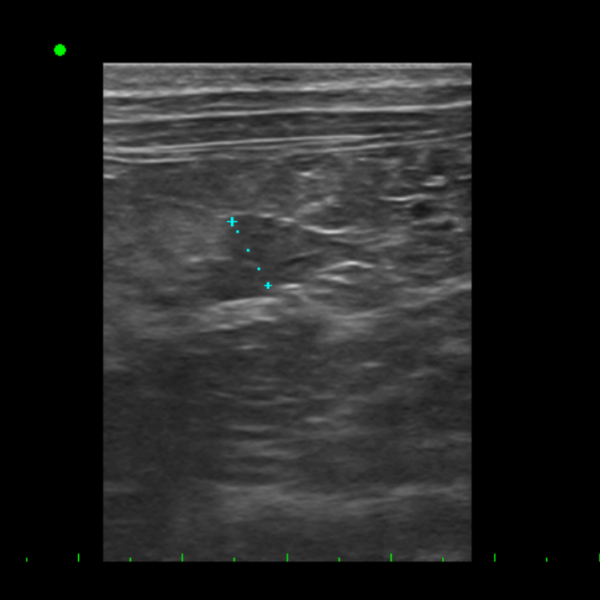

복부 초음파 검사에서는 비장 내 작은 결절과

췌장·장·방광 주변 경미한 변화가 확인되어

고양이 항암 검사 상 전이 가능성을 완전히 배제하기 어려운 상태였습니다.